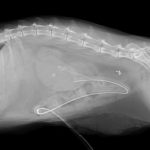

尿管結石による急性の腎障害で腎数値が顕著に上昇しているというマンチカンちゃんが手術のために来院しました。CTで確認すると複数個の結石が尿管内に存在しています。この問題に対して顕微鏡下で尿管膀胱新吻合と短尺型(カスタムメイド)尿管ステントを設置しました。36時間後には腎数値も改善しました。長時間の手術となりましたがよく頑張ってくれました。